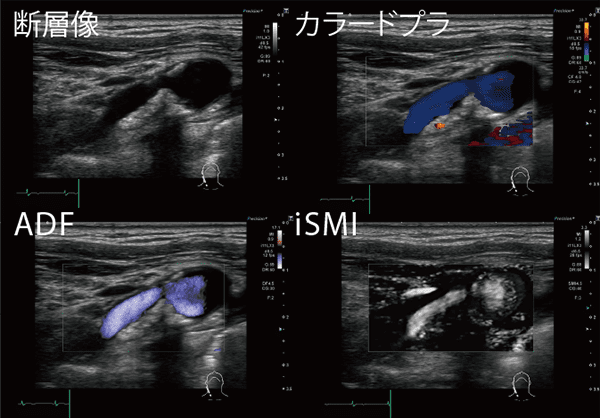

Aplio iシリーズに実装されたiSMI(Superb Micro-vascular Imaging)では、低流速血流をより明瞭に描出可能となった。脳梗塞におけるiSMIの有用性について濵口部長は、「iSMIでは微細な血流を観察でき、プラーク内新生血管の性状評価も可能なため、脳梗塞の治療方針決定にとても有用です。また、境界面を明瞭に描出可能なことから、プラークの見落としが減少したことに加え、内膜剥離術やステント留置術の術後で、血管内腔や血管壁の詳細な情報がほしい場合にも役立ちます」と話す。

さらに、iSMIと24MHzリニアプローブを組み合わせることで、5mmより浅い領域の血流の観察も可能になった。脳梗塞診療における有用性について濵口部長は、「浅側頭動脈と中大脳動脈のバイパス術において重要な、浅側頭動脈の情報を取得できます。また、心原性脳塞栓症では心内血栓が手足の動脈も閉塞する場合があるため、指先の血流を確認して急性動脈塞栓の診断補助にも用いています」と説明する。